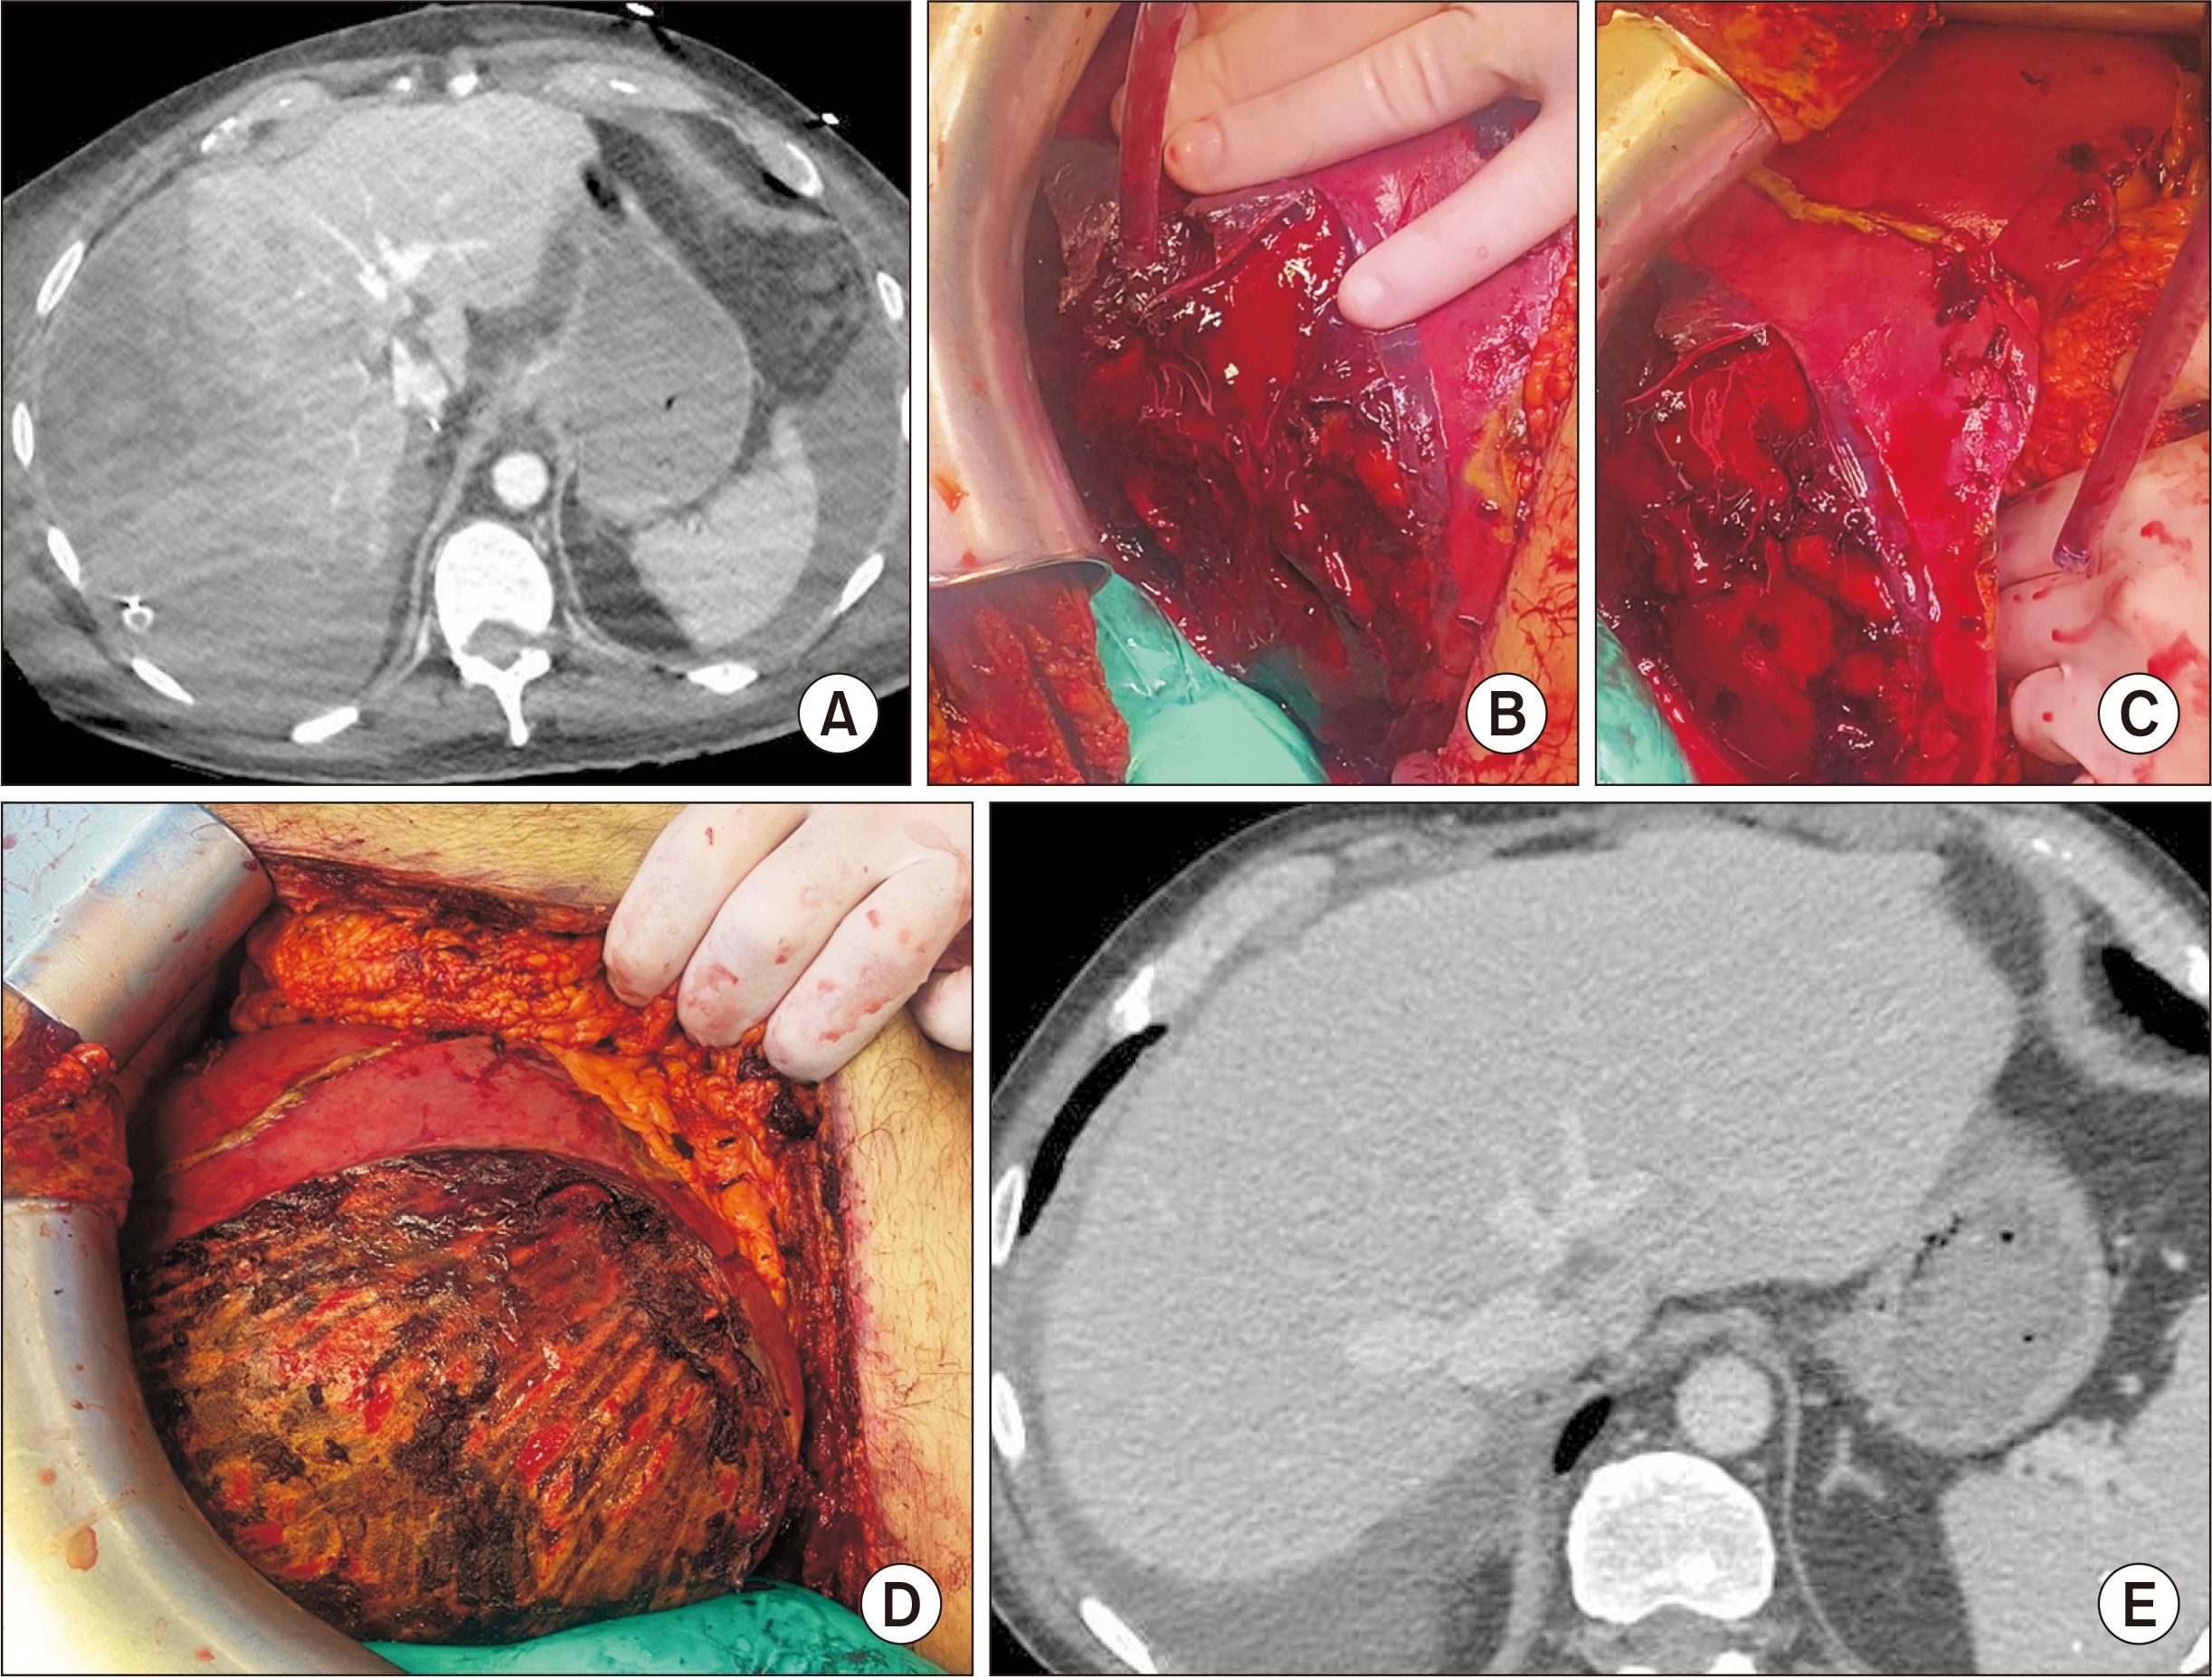

- Hepatic compartment syndrome (HCS) is a rare but life-threatening entity that consists of a decreased portal flow due to intraparenchymal hypertension secondary to subcapsular liver hematoma. Lethal liver failure can be observed. We report three cases, and review the literature. A 54-year-old male was admitted for extensive hepatic subcapsular hematoma after blunt abdominal trauma. Initially, he underwent embolization of the hepatic artery’s right branch, after which he presented clinical deterioration, major cytolysis (310 times the upper limit of normal [ULN]), and liver failure with a prothrombin time (PT) at 31.0%. A 56-year-old male underwent liver transplantation for acute alcoholic hepatitis. On postoperative day 2, he presented a hemorrhagic shock associated with deterioration of liver function (cytolysis 21 ULN, PT 39.0%) due to extensive hepatic subcapsular hematoma. A 59-year-old male presented a hepatic subcapsular hematoma five days after a cholecystectomy, revealed by abdominal pain with liver dysfunction (cytolysis 10 ULN, PT 63.0%). All patients ultimately underwent urgent surgery for liver capsule excision, hematoma evacuation, and liver packing, if needed. The international literature was screened for this entity. These three patients’ outcomes were favorable, and all were alive at postoperative day 90. The literature review found 15 reported cases. HCS can occur after any direct or indirect liver trauma. Surgical decompression is the main treatment, and there is probably no place for arterial embolization, which may increase the risk of liver necrosis. A 13.3% mortality rate is reported. HCS is a rare complication of subcapsular liver hematoma that compresses the liver parenchyma, and leads to liver failure. Urgent surgical decompression is needed.